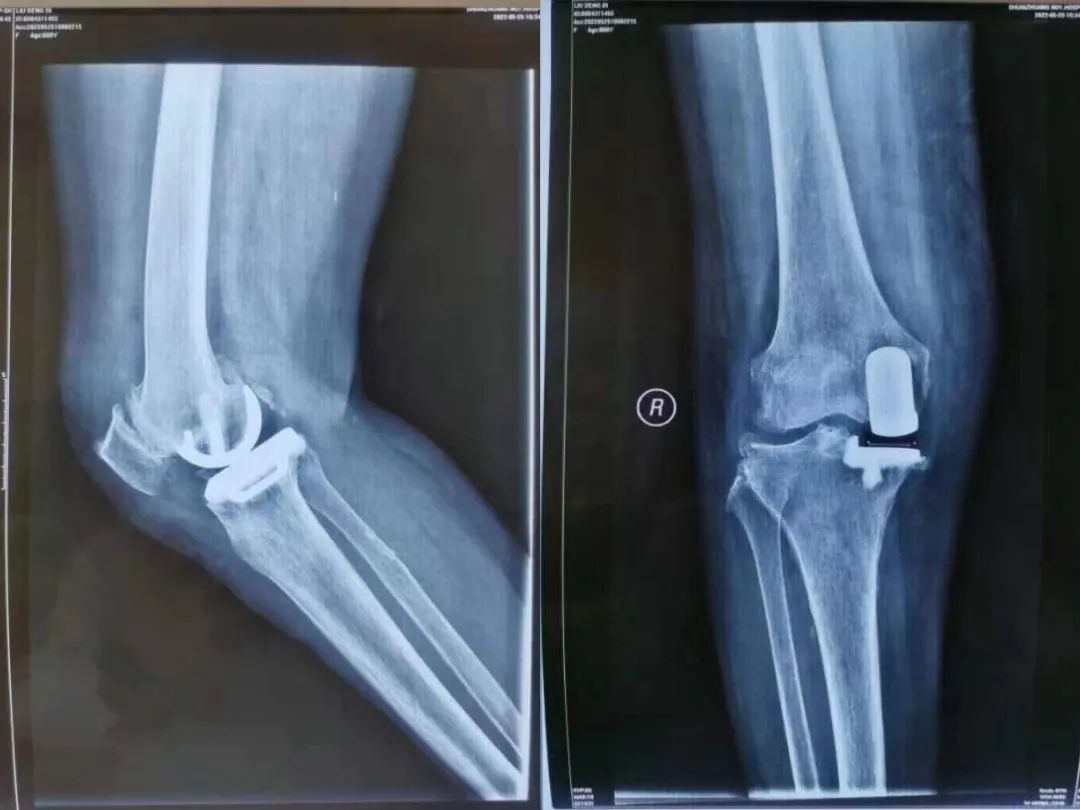

結(jié)合診斷結(jié)果和個(gè)體情況,李軍勇主任為劉奶奶設(shè)計(jì)了『保膝』方案——右膝微創(chuàng)單髁置換手術(shù),此手術(shù)最大的特點(diǎn)就是切口小,出血少。采取此方案,老人既能耐受手術(shù),又可以直擊病灶,最大程度保留自身膝關(guān)節(jié)的外側(cè)部分軟骨以及韌帶功能,保留膝關(guān)節(jié)的本體感覺。

術(shù)后僅僅第二天,老人因?yàn)樘弁炊D昃o皺的眉頭終于舒展開了,劉奶奶嘗試著在輔助下行走,術(shù)后膝關(guān)節(jié)疼痛癥狀基本緩解,術(shù)后三天便出院回家了。被『保住』的膝關(guān)節(jié)得到了修復(fù),極大程度提高了老人的運(yùn)動(dòng)能力,改善了老人生活質(zhì)量。